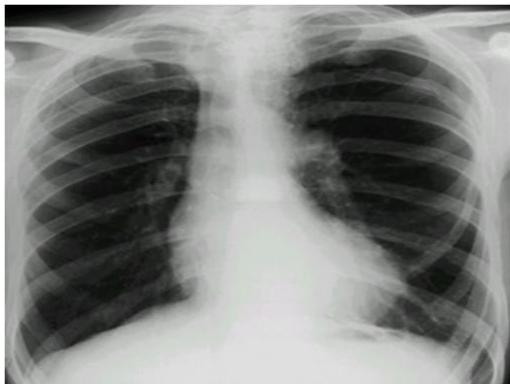

Asthma with Pneumothorax / Emphysema (CXR)

in This PIC Be Curfiat → Check Countage of the lung

Hint: Loss of contour of lung

- Check if hyperinflated

The hint is loss of Couture of lung in the emphysema → we doubt see?

Scenario: 5 year old with 3 days of acute asthma, progressive SOB, cyanosis.

CXR findings?

- Right-sided pneumothorax (or horizontal pneumothorax), subcutaneous emphysema, with left mediastinal shift

- Loss of lung opacity

- Mucous plug causing collapse/obstruction

- Other mentions in original: “Liver & mucus”, “Pneumonitis”

Examination Findings (Chest):

- Hyperresonance (increased sound on percussion)

- Pulsus paradoxus

- Decreased breath sounds

Management?

- Address the underlying cause (e.g., decompression for pneumothorax, airway clearance)

- Bronchodilator, inhaled steroid

- Suction + physiotherapy

- If pneumothorax: chest tube — 5th intercostal space, anterior axillary line

- Possible intubation